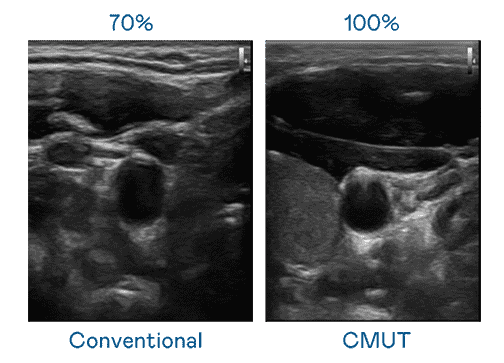

CMUT 技术是一种用电容式微机电元件来产生超音波讯号的技术。。。。与传统 PZT 压电式技术相比,,CMUT 频宽增加 30%,,,,更宽频的超音波讯号让影像解析度大幅提升,,是实现高影像品质医疗超音波扫描、、、、促进精准医疗发展的关键技术。。。。

超音波影像的解析度高低,,首先取决于探头能发出的讯号频宽。。。至成国际 CMUT 可提供高清晰的超音波讯号,,,提供高频宽、、、高灵敏度、、影像纹理细节更高的超音波影像,,协助医护人员缩短影像判读时间及利用精准的医疗影像进行诊断。。。